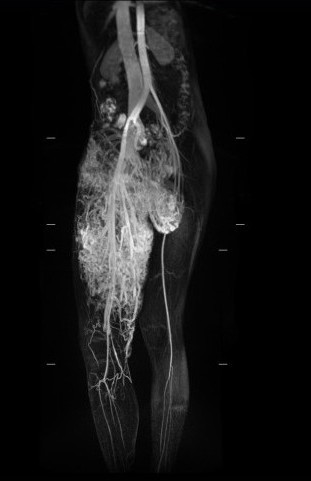

小班克雖然有爸爸、慈濟志工符玉鸞、翻譯志工陳碧玲等人的陪伴,但面對一連串的X光、磁振造影、血管攝影等等檢查,不免還是會不安。尤其是在影像醫學部張寶源醫師為小班克進行血管攝影檢查時,沒有做過相關檢查的她,半身麻醉的疼痛與緊張,導致她過度換氣,為了安撫班克的情緒,醫療團隊除了趕緊請爸爸阿肅穿上鉛衣進到攝影室裡陪伴,並透過手機播放與寮語相近的泰文歌曲,幫助班克放鬆心情,終於讓她情緒緩和,順利地完成血管攝影檢查。

小班克的所有檢查順利完成,十一月六日,在陳培榕副院長的召集下,召開醫療團隊會議,由陳培榕副院長召集整形暨重建外科、影像醫學部、放射腫瘤科、護理部等醫療團隊,以及社會服務室主任與顏靜曦師姊,並邀請基金會劉濟雨副執行、宗教處同仁協同參與。陳培榕副院長表示,透過血管攝影檢查,發現小班克右腿的動脈與靜脈沒有經過微血管就直接相接是「動靜脈畸形」,這是最不容易處理狀況。

李俊達主任表示,小班克除了腿間的動靜脈畸形瘤,在下腹部、鼠蹊部、大腿大部分是動靜脈畸形,也是造成右大腿腫大的原因。而大腿深部的動脈與靜脈連接在一起,加上包覆大腿皮膚表層的微血管畸形面積很大,若使用雷射方式移除,得進行十次以上的雷射手術,還可能引起大出血;另一種治療方式則是使用栓塞手術,但可能會造成皮膚潰爛或引起併發症,若要全部移除是較為困難。

為了找出適合小班克的治療方式,李俊達主任及整形外科團隊也與陳明庭教授、戴浩志主任、臺大醫院影像醫學部腹部影像診斷科梁博欽主任多次討論,決定在十二月六日先與梁博欽主任一起為小班克進行血管栓塞手術,並請麻醉部疼痛科主任王柏凱協助,讓小班克在全身麻醉的情況下進行,以降低小班克的恐懼,李俊達主任說,目前影響小班克最大的是位於鼠蹊部的腫瘤,透過血管栓塞手術減少腫瘤的血液供給量,讓移除腫瘤術式能進行的更順利,也能避免失血過多的情況發生。